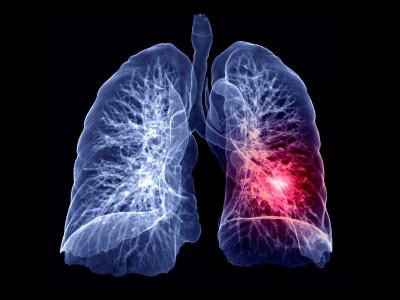

फुप्फुसात रक्ताची गाठ - छातीमध्ये वेदना होण्याचं कारण पल्मोनरी एम्बोलिज्मही असू शकतो. या आजारात फुप्फुसाच्या नसांमध्ये रक्ताच्या गाठी तयार होतात. ज्यामुळे टिश्यूमध्ये पोहोचणारा रक्तप्रवाह स्लो होतो.